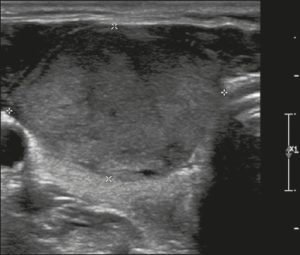

Ở đây, chúng tôi cung cấp các ví dụ minh họa việc áp dụng thực tế hệ thống ACR TI-RADS (Hình 18, 19, 20, 21). Các chú thích dưới hình mô tả chi tiết các mục đã được đánh giá và hiển thị điểm số trong ngoặc đơn.

Hình 20. Hình ảnh nhân giáp hỗn hợp đặc và nang (1 điểm), đồng âm (1 điểm), rộng hơn cao (0 điểm), và lan rộng ra ngoài giới hạn phía trước của tuyến giáp (3 điểm), không có các ổ tăng âm hay bóng lưng (0 điểm). Do đó, tổng điểm là 5 điểm và mức độ nguy cơ được phân loại là TR4.